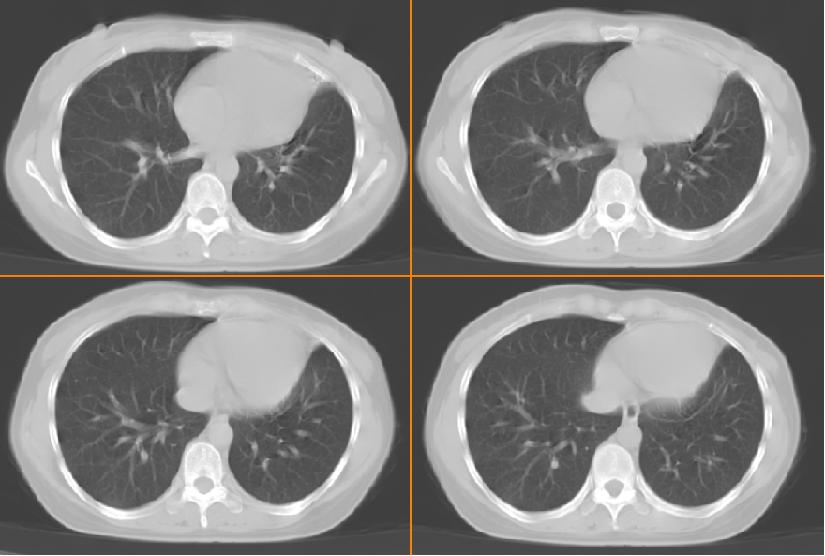

女,33岁,咳嗽5月。

双上肺、左下肺背段肺结核,左上肺膨胀不全.

左肺上叶前段致密,内见空气支气管征,相应部位胸膜增厚粘连,双肺上其他肺叶不同程度斑片状播散病灶,结合咳嗽5月的病史,考虑:双肺上叶继发性肺结核伴左肺上叶肺含气不良。